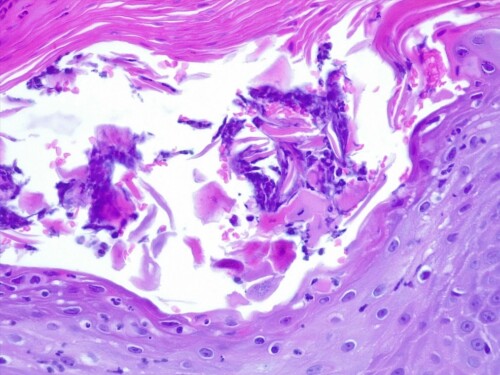

L’examen histologique des coupes de lésions croûteuses colorées à l’hématoxyline et à l’éosine révèle une hyperplasie parakératosique, avec de petites vésiculo-pustules intra-épidermiques contenant des éosinophiles et quelques cellules épithéliales acantholysées, un infiltrat lichénoïde avec des lymphocytes, des plasmocytes, des macrophages, des cellules dendritiques et des mélanophages dans les machons péri-annexiels. Aucun élément bactérien ou parasitaire n’est observé.

Figure 3: Agrandissement plus important. Vésiculo-pustules intra-épidermiques contenant des éosinophiles et quelques cellules épithéliales acantholysées (H&E x400).